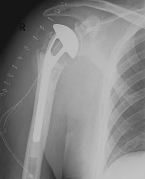

Abbildung6Conventional stem prostheses for omarthrosis and acetabular wear

left: X-ray image of a shaft prosthesis

right: anatomical shoulder prosthesis with glenoid replacement (Affinis type, Mathys company)